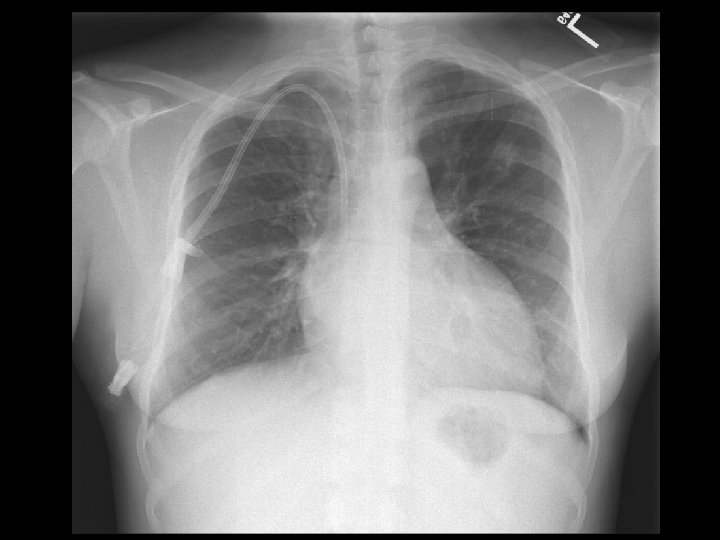

Left hydropneumothorax • Findings: – left pnuemothorax – left pleural effusion (possibly blood) • causes: – penetrating trauma – iatrogenic – bronchopleural fistula